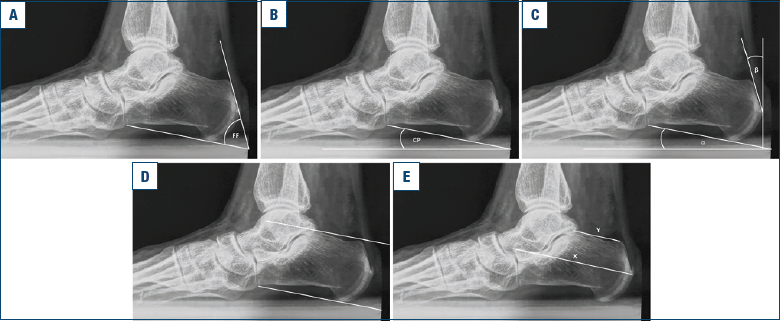

Una radiografia sotto carico del piede è l’esame di primo livello, che permette di evidenziare la presenza di una prominenza postero superiore del calcagno, e di eventuali ossificazioni inserzionali intra tendinee. Questa permette anche le misurazioni necessarie (Fig. 3).

- L’angolo di Fowler-Philip è disegnato tra la tangente alla faccia inferiore del calcagno dal tubercolo postero-mediale alla calcaneo-cuboidea, e la tangente alla faccia posteriore della grande tuberosità calcaneare. L’angolo normale si considera di 44-69°, mentre un angolo > 75° è considerato patologico 14.

- Il calcaneal pitch è disegnato tra la tangente alla faccia inferiore del calcagno e il terreno. Un angolo di 15-18° è considerato normale, mentre oltre i 30° il valore è sicuramente patologico 15.

- L’angolo di Chauveaux è la differenza tra gli angoli alfa e beta, dove alfa è il calcaneal pitch, mentre beta è l’angolo tra la perpendicolare al terreno passante per il punto più posteriore del calcagno, e la tangente alla tuberosità posteriore passante per questo stesso punto. I valori normali sono < 12° 16.

- Le linee parallele di Heneghan-Pavlov sono una linea inferiore tangente alla superficie plantare del calcagno e passante per il punto più basso della calcaneo-cuboidea, e una parallela a questa, passante per il limite posteriore dell’astragalo calcaneare. La proiezione superiore della grande tuberosità calcaneare è patologica se supera la linea superiore 17.

- la X/Y ratio è definita da X, che è la lunghezza maggiore del calcagno, dal punto più anteriore dell’apofisi anteriore al punto più posteriore della grande tuberosità (escluse le calcificazioni), e da Y, che è la lunghezza della grande tuberosità, dal punto più posteriore dell’astragalo calcaneare fino alla sommità della grande tuberosità. Il rapporto indica la lunghezza calcaneare relativa. Un valore < 2,5 indica una deformità di Haglund 18.

Figura 3. Misurazioni radiografiche della deformità di Haglund: (a) angolo di Fowler-Philip; (b) calcaneal pitch; (c) angolo di Chauveaux; (d) linee parallele di Heneghan-Pavlov; (e) X/Y ratio.